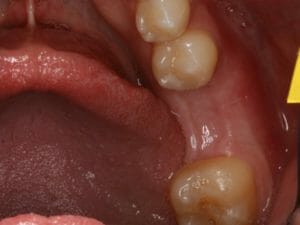

Ridge Augmentation

Sometimes the bone is severely reduced by trauma, infection or extended time without a tooth. When this occurs, that bone needs to be rebuilt in a process called Ridge Augmentation. For this, bone graft materials must be placed under the gum tissue and shaped into the form of the original bone. A dissolvable membrane is used to keep the bone graft protected. Sometimes, biological growth factors may be added to enhance the bone growth. Dr. Kuznia and Dr. Storch typically wait between 4 and 6 months before augmented bone is ready to hold a dental implant.